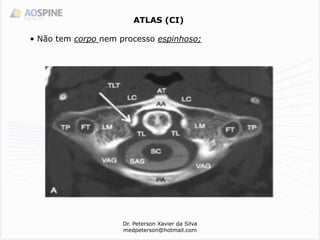

ATLAS (CI)

• Não tem corpo nem processo espinhoso;